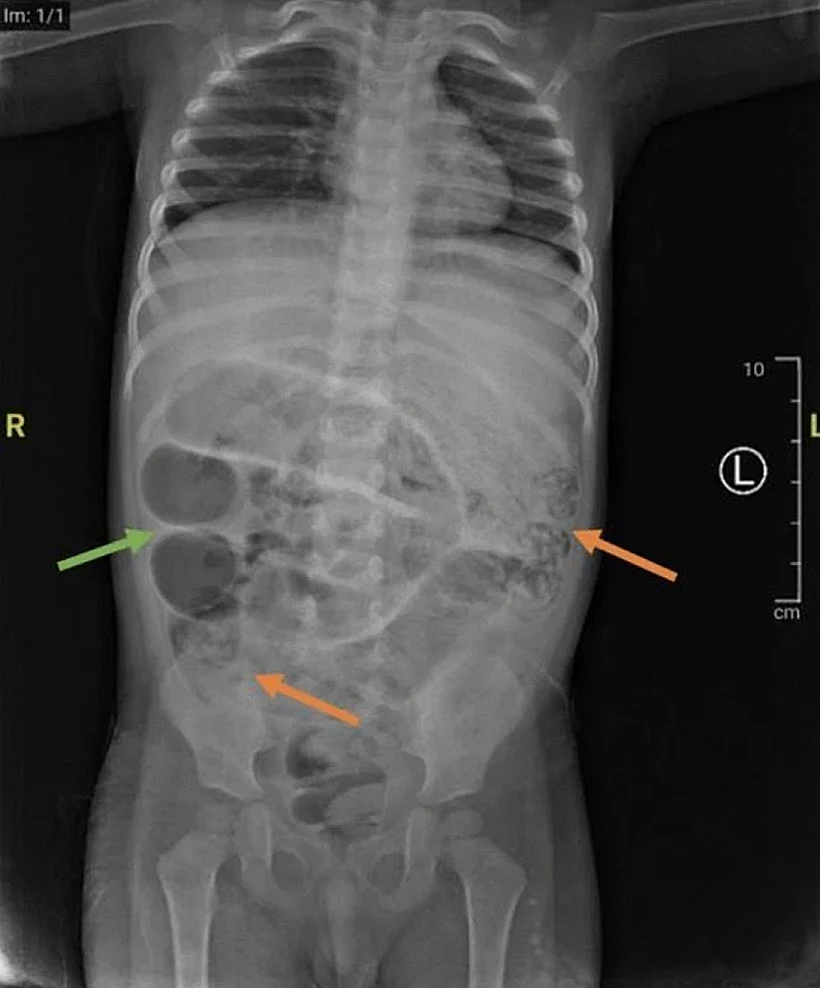

בבדיקה ראשונית, הרופאים חשבו שמדובר בעצירות בלבד, אך כעבור יממה הילד החל להקיא תולעים. בדיקות רנטגן חשפו מסות אפורות במעי של הילד, מה שהתברר בהמשך כחסימה חמורה במעי הדק.

הילד הובהל לניתוח חירום, במהלכו נמצאו תולעים בשלושה אזורים נפרדים במעי הדק. התולעים זוהו כ-Ascaris Lumbricoides – תולעים עגולות שיכולות לחיות במערכת העיכול של בני האדם, ולהגיע לאורך של עד 35 ס"מ.

הרופאים ביצעו חתך קטן בדופן המעי של הילד, כ-50 ס"מ מהמעי הגס, ושלפו את התולעים בעדינות מגופו. לאחר מכן, המעי נתפר מחדש, והתולעים נשלחו לבדיקה מעבדתית. הילד טופל באנטיביוטיקה, ושוחרר מבית החולים כשבוע לאחר מכן.